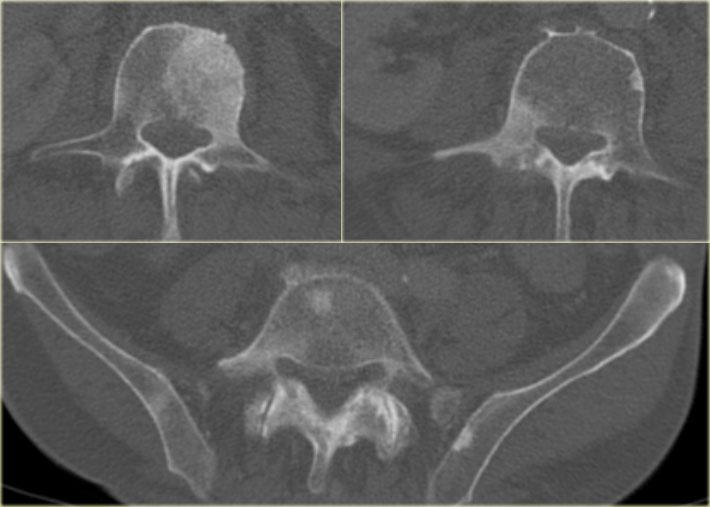

- Sự phát triển của u xương sụn ở các vị trí trung tâm như khung chậu, hông và vai là phổ biến nhất.

Cần xem xét u sụn ngoại vi ác tính trong các u xương sụn đang phát triển có hoặc không có đau sau khi đóng tấm sụn tiếp hợp.

Dấu hiệu X-quang hoặc CT gợi ý ác tính:

- tăng trưởng u xương sụn ở bệnh nhân xương đã trưởng thành

- bề mặt tổn thương không đều hoặc không rõ ràng

- ăn mòn hoặc phá hủy xương lân cận

- khối phần mềm với vôi hóa rải rác hoặc không đều

Dùng MRI với chuỗi xung nhạy cảm nước (T2 FS) để xác định độ dày mũ sụn.

Cân nhắc ác tính hóa u xương sụn thành ung thư sụn xương khi mũ sụn > 10 mm.